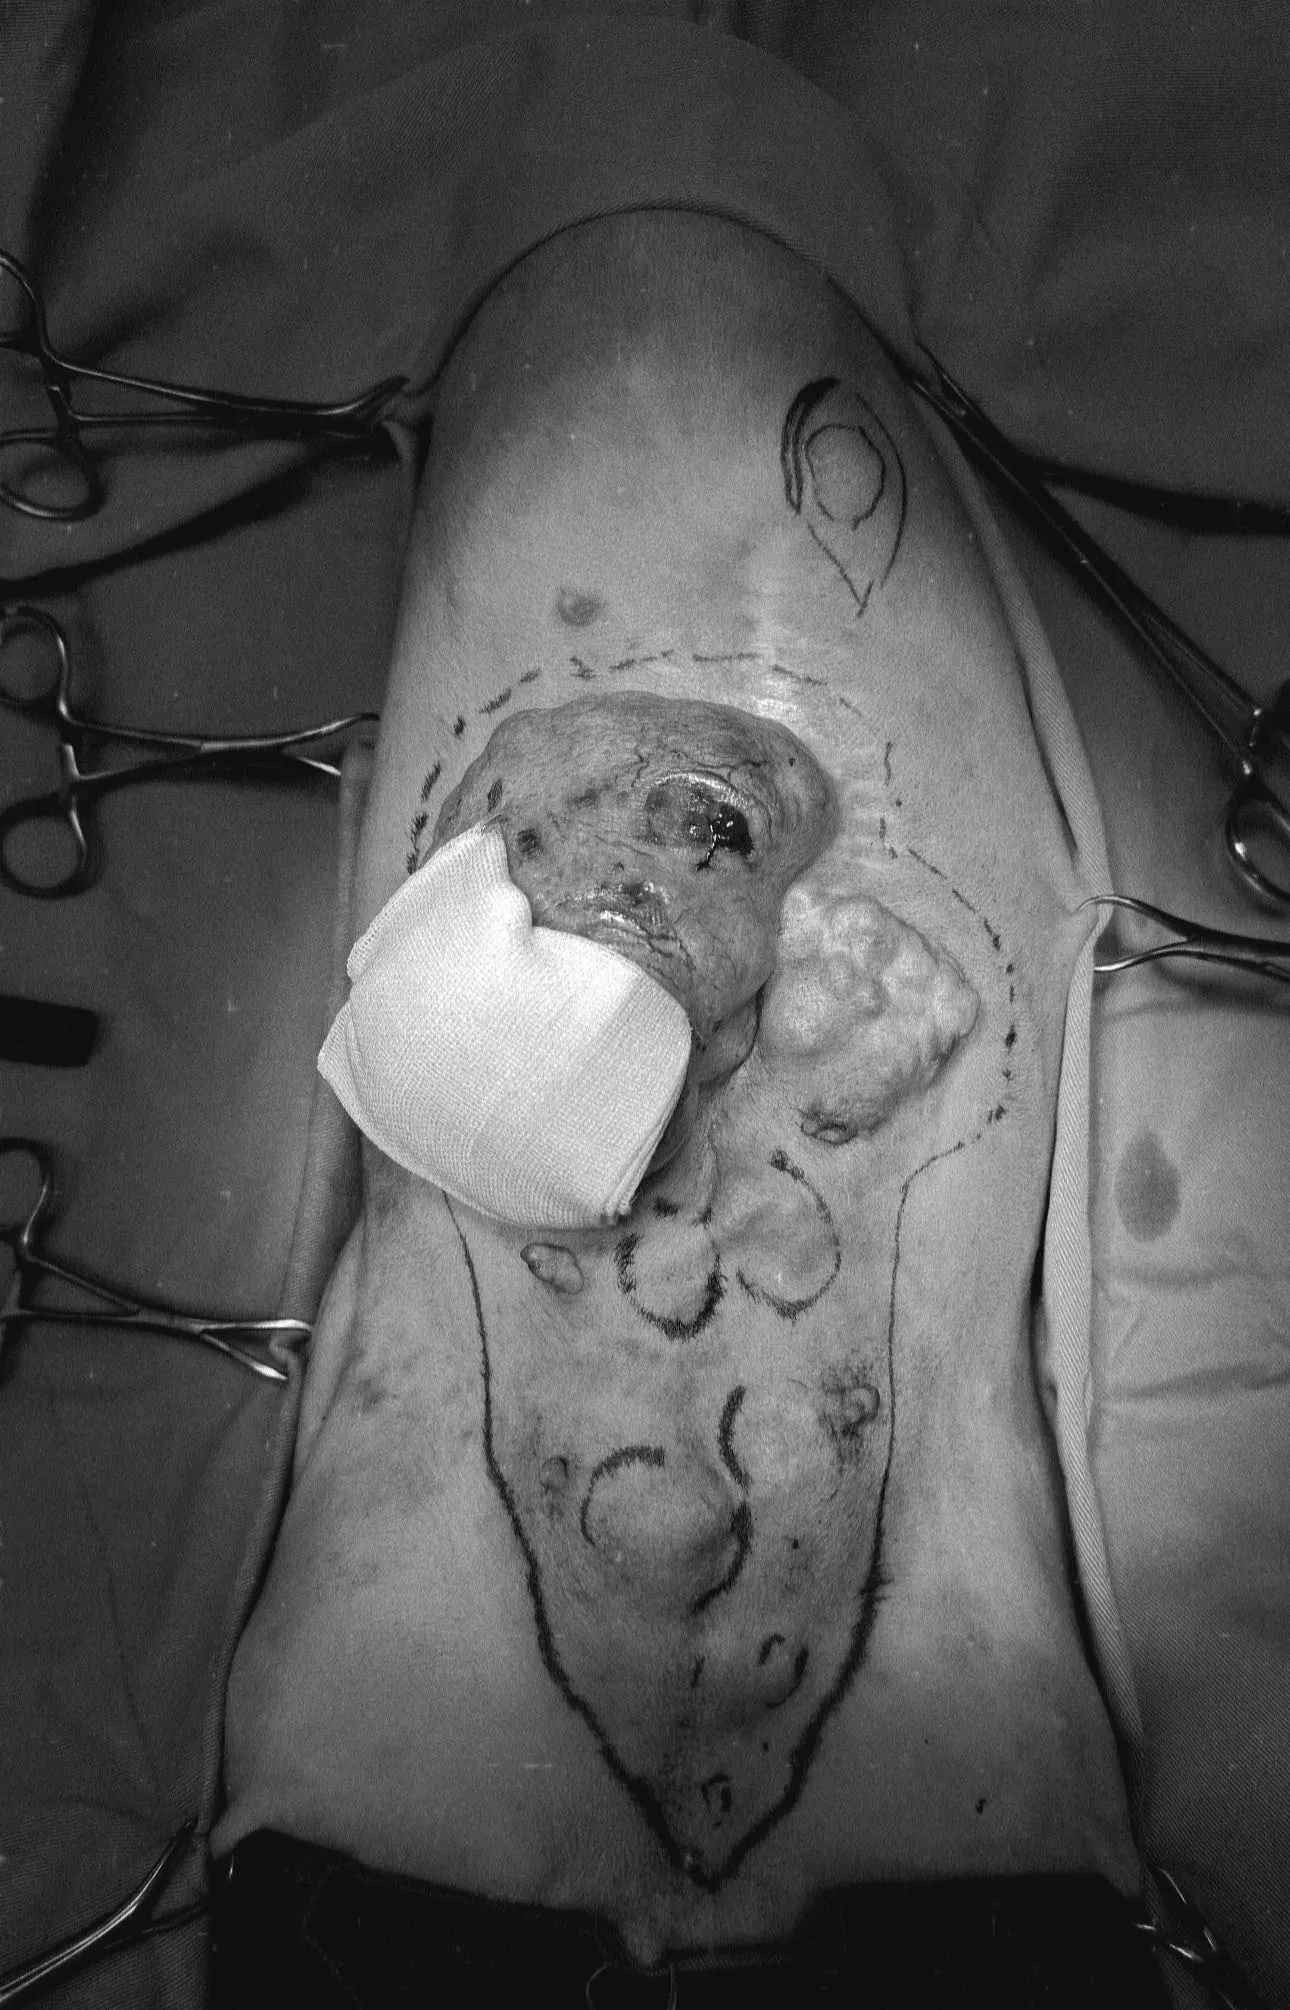

今天分享的病例是一隻大黑狗老爺爺,前一陣子因為不明原因的虛弱、貧血,檢查的時候發現脾臟有大型腫瘤,在穩定身體狀況之後很快安排手術拆彈,切片還發現了腫瘤內部疑似還躲藏細菌 !

今天分享的病例是一隻大黑狗老爺爺,前一陣子因為不明原因的虛弱、貧血,檢查的時候發現脾臟有大型腫瘤,在穩定身體狀況之後很快安排手術拆彈,切片還發現了腫瘤內部疑似還躲藏細菌

幸好在未引爆的情況下拆除,狗狗術前術後都不需要輸血,貧血的狀況與發炎指數都在術後徹底改善了 !